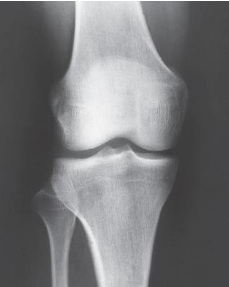

What Knee projections is this

AP Knee

Patient position for AP Knee

supine, no pelvic rotation

In AP Knee, the femoral epicondyles are what to the IR

parallel

The CR in Knee projections are variable depending on the what

ASIS

If Patient’s ASIS is less than 19cm from the table, then the CR angling would be

3 to 5 degrees caudal

If Patient’s ASIS is more than 24cm from the table, then the CR angling would be

3 to 5 degrees cephalic

If Patient’s ASIS measures 19 to 24cm from the table, then the CR angling would be

0 degrees

The CR in an AP knee enters

½ inch below pateller apex

Radiation field for AP Knee is

10 × 12 inch LW

The Patella superimposed on the femur (will

lie slightly to the medial side) is seen on